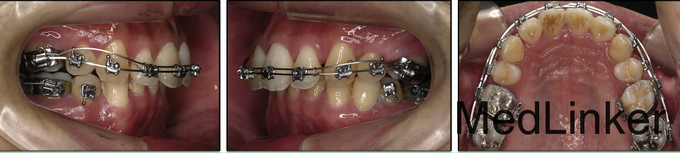

诊断:骨性II类,安氏II类,牙列间隙 治疗:上颌先上.022直丝拖槽,14niti排齐整平,依次换丝,为打开前牙咬合,16*22TMA弯制压低辅弓,如图。打开咬合后,粘接下颌拖槽,继续矫正。

压低辅弓不直接就位于前牙拖槽内,而是结扎在前牙段弓丝上,与前牙呈点状接触,属于单力偶力学系统,根据压低的部位不同可结扎在不同的牙位上达到选择性的压低,若压低前牙的话,可稍向后结扎如扎于23之间,可更接近前牙段阻力中心,减少其压低时唇倾的副作用。